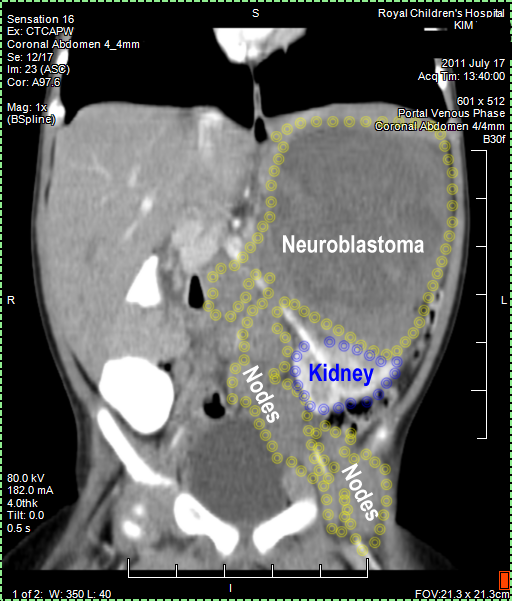

CT (CAT) scan 17July 2011